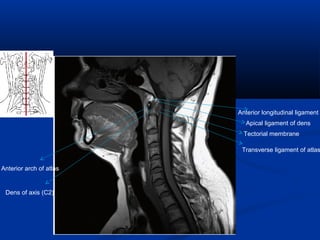

Anterior longitudinal ligament

Apical ligament of dens

Tectorial membrane

Transverse ligament of atlas

Anterior arch of atlas

Dens of axis (C2)